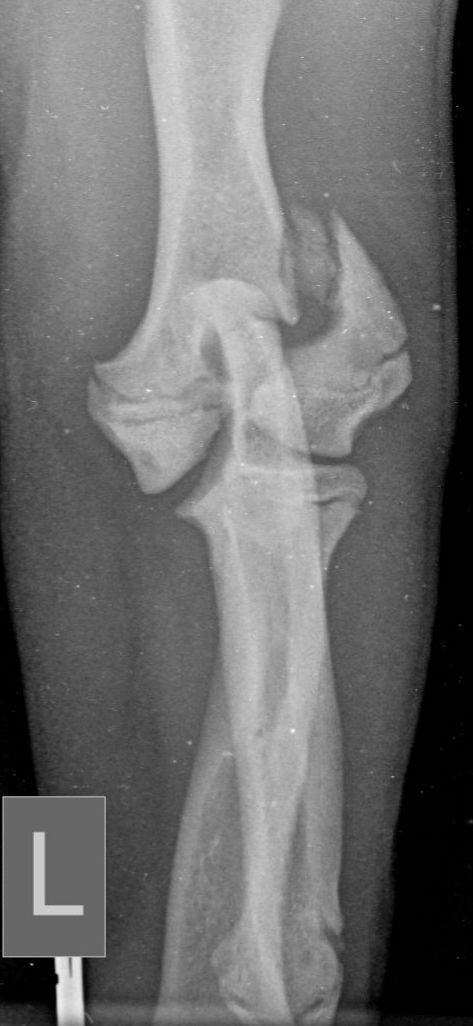

These concerns have led to recommendations being altered over the past decade or so, with veterinarians now using bone plates, instead of K-wires, as an adjunct to a transcondylar screw when managing humeral unicondylar fractures (Figure 2), even in puppies (Figure 3) (Clark, 2016; Kvale et al., 2022). However, the basis on which this conclusion for puppies was reached appears to have been flawed because it assumed that what had been shown to be the case for adults would also apply to immature patients. As the conclusion was felt to conflict with the author’s experience of treating such patients, a retrospective study was undertaken to evaluate complications and outcomes in immature dogs treated for humeral unicondylar fractures at one centre over a 10-year period (Butterworth, 2022). The findings of this study are summarised in this article.

Therefore, if the current trend towards the use of epicondylar plates, rather than K-wires/pins, in combination with a transcondylar bone screw to manage humeral unicondylar fractures in adults is also adopted for skeletally immature patients, we might well be throwing the puppy out with the bath water. The exception might be when the epicondylar ridge shows comminution, which means that a single K-wire might not provide enough stability, or when the patient shows prodromal lameness (both of which were noted in the patient related to Figure 3).